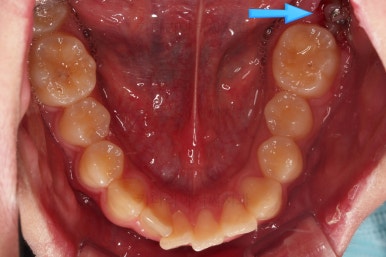

구멍이 뻥 뚫린게 보이실거에요.

매복 사랑니를 발치한 자리입니다.

사랑니를 발치하며 앞쪽에 살려 써야하는 어금니에 작은 장치를 부착했어요.

어금니를 당겨줄 미니스크류도 사랑니를 발치하면서 식립해 주었어요.

매복치아였기 때문에 입 안에서는 장치도 거의 보이질 않죠.

해당 장치와 미니스크류 사이에 교정용 고무줄을 연결하여 지속적으로 당겨줍니다.